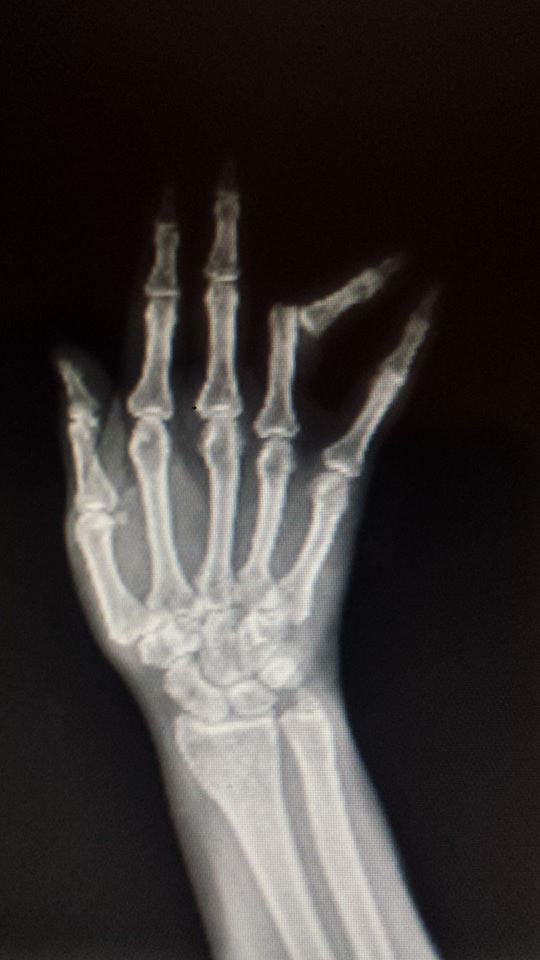

Las lesiones en las manos son comunes y pueden ocasionar un tiempo de inactividad prolongado. Para analizar e identificar los factores que afectan el tiempo de trabajo, se necesita una visión holística de los pacientes. La Clasificación Internacional del Funcionamiento, la Discapacidad y la Salud (ICF) de la Organización Mundial de la Salud con su perspectiva biopsicosocial brinda una visión tan holística. El propósito de este estudio es analizar el tiempo de ausencia de trabajo en pacientes con lesiones traumáticas en las manos e identificar los factores que afectan el tiempo libre del trabajo desde una perspectiva biopsicosocial.

En total, se incluyeron 231 participantes del estudio con una amplia gama de lesiones en las manos. De estos, 178 pacientes (77%) regresaron al trabajo en 200 días. Las deficiencias en la movilidad de las funciones de la articulación y las funciones sensoriales relacionadas con la temperatura y otros estímulos, así como una mayor tensión de la mano en el trabajo, condujeron a un tiempo de inactividad prolongado. El género, el buen uso de la mano y el estado laboral también influyeron en el tiempo de descanso en los submodelos. Nuestros resultados demuestran que se recomienda una perspectiva biopsicosocial cuando se investiga el tiempo de inactividad prolongado.